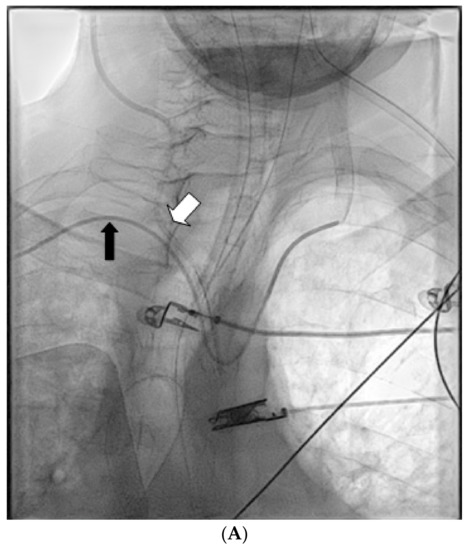

Emergency CT angiography confirmed that the catheter had transversed the internal jugular vein and had been inserted into the right subclavian artery. Ultrasound Doppler examination of the right upper extremity confirmed presence of a biphasic signal in the brachial radial and ulnar arteries. Following vascular surgical and interventional radiology consultation, intravascular balloon tamponade with concurrent external pressure application was decided as the preferred method for safe catheter removal. The patient was transported to the Interventional Radiology Unit, (Figure 1A) where an 8 × 40 mm Mustang angioplasty balloon (Boston Scientific, Marlborough, MA, USA) was inserted through the right brachial artery, which was immediately inflated after the CVC removal, providing internal balloon tamponade while simultaneous external pressure was applied to the insertion site for 5 min. Subsequent angiography revealed no leaks or fistulae (Figure 1B). No further complications from the accidental intra-arterial catheter insertion were noted. On the 18th day of ICU stay, the patient was discharged to the Neurology Department, with a GCS of 10/15 (Eye: 4/4, Motor 5/6, Verbal: 1/5) and neurological findings similar to those noted on hospital admission.

Figure 1. (A) CT angiography confirming right subclavian artery catheterization, just distal to the origin of the right vertebral artery. (B) Final result after removal of the CVC with no extravasation.